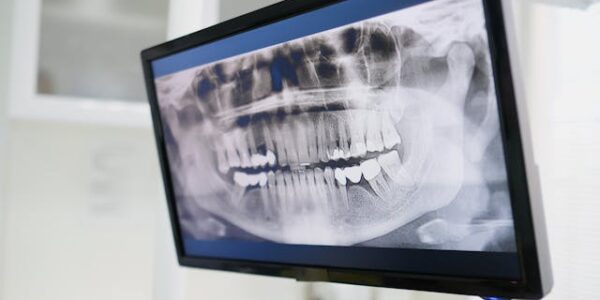

Co można wykryć na RTG zębów?

Badanie RTG zębów, czyli rentgenodiagnostyka stomatologiczna, to jedno z podstawowych narzędzi wykorzystywanych przez dentystów do oceny stanu jamy ustnej. Choć samo zdjęcie RTG jest szybkie i nieinwazyjne, dostarcza ono wielu cennych informacji, których nie da się uzyskać w czasie rutynowego…